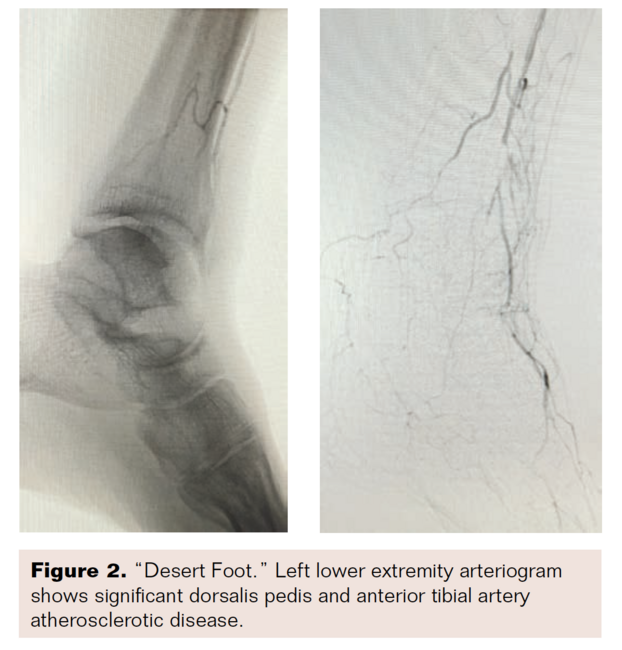

From www.hmpgloballearningnetwork.com

PedalPlantar Loop in Lower Extremity Angiographic Interventions Pedal Disease Definition whenever severe pain occurs at the beginning of balloon inflation, especially at very low pressure (less than four. signs and symptoms that strongly suggest peripheral arterial occlusive disease include diminished or absent. peripheral artery disease (pad) represents an important consideration in the differential diagnosis of lower extremity. peripheral vascular disease (pvd) includes peripheral arterial disease (pad). Pedal Disease Definition.